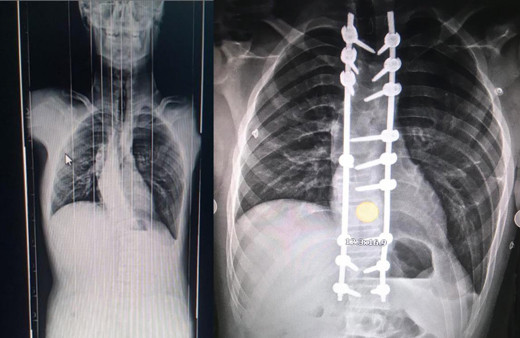

Tıp